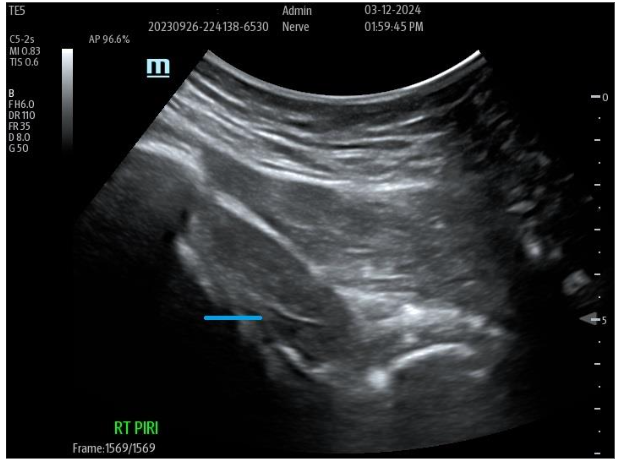

Many examples of important epineural-dissections and fascial inflammatory conditions have been improved with applications of a biocellular mixture, including use of PPP products are becoming a very common, safe and effective protocols. Often by “resting” simulated, entrapped or irritated peripheral sensory nerves, long-term relief is attained. This is considered partially due to fibrin conversion which may provide addition protection while reducing the nerve axonal irritation. This has become a more effective and commonplace option, particularly in areas such as inflamed fascia as in the thoraco-lumbar fascial (TLF), Piriformis/Sciatic areas, and Ilio-Tibial Band (ITB). The PPP or biocellular elements are also capable of providing soothing impacts of the area, plus helping limit inflammatory response and promote recovery. It may be a combination of the anti-inflammatory action of the stem/stromal cells and the fibrinogen contained to form a fibrin protection of irritated nerve structures often missed in regenerative efforts and not available in invasive surgical procedures.

Figure 9A: Pre-Treatment U/S of degenerative Piriformis (sciatic radicular symptoms) no history of trauma, degenerative Pattern within Piriformis musculature with loss of muscle echotexture. Figure 9B: Post-treatment of site at nine months post-treatment with tSVF + HD PRP (70% tSVF: 30% HD PRP (6X – concentration HD PRP) with return of improved muscular echotexture and elimination of radicular sciatic symptoms.